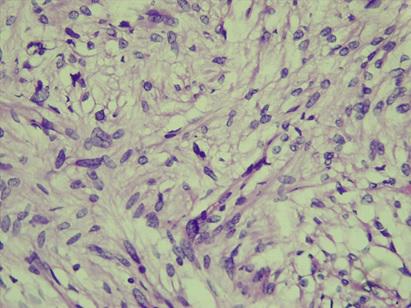

* Case 10: Dr Nathan McGrath (University of the Witwatersrand)

email: nathmcg@gmail.com

Clinical detail: A 53-year-old female, para 2 gravida 2, was referred to the gynecology department at CHBAH with seven years history of menorrhagia, dysmenorrhea, and symptomatic iron deficiency anemia.  The patient had an enlarged, irregular uterus and a transvaginal ultrasound examination showed multiple solid hypo-echoic intramural and subserosal masses, in keeping with a multifibroid uterus. Due to persistent symptoms, an elective total abdominal hysterectomy was performed.